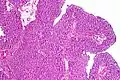

Histopathology of urothelial carcinoma of the urinary bladder.